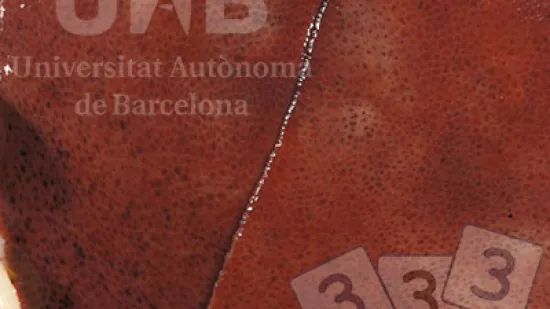

Semaine du 18-Jan-2022

Les points rouges observés au centre des lobules hépatiques sont évocateurs de...